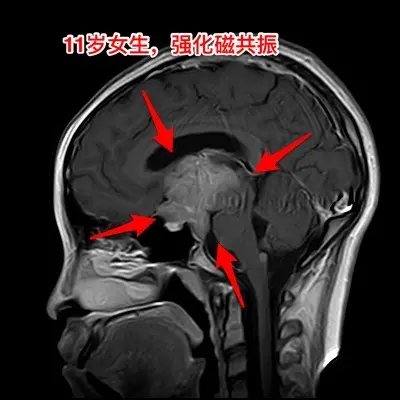

生殖细胞瘤对化疗很敏感,降低颅压才安全。之前我发的11岁四川女孩子,因多饮多尿、视力下降、多睡等症状在我科住院。住院后经用药物治疗,精神状态明显好转。 我们怀疑肿瘤为生殖细胞瘤,因肿瘤体积巨大,综合考虑病史、体检、手术风险、对化疗、放疗的敏感性,我们于8月13日给患儿作了肿瘤活检手术。 手术后病理报告为纯生殖细胞瘤,未见其他肿瘤成分(当然活检取得的标本很少,这个结论不是百分百的可靠) 8月20日开始化疗,8月21日患儿出现精神差、多睡症状,和住院前的症状相似。复查CT显示肿瘤在活检手术后继续增大,而且造成了脑积水,颅压高,见图2。此时不得不为患儿作急诊脑室外引流手术,以求降低颅压,为化疗保驾护航。随后继续化疗。 化疗的第三天,CT显示肿瘤体积有所缩小,见图4。 化疗一周后,肿瘤体积显著变小了,脑积水明显减轻了,见图5。病人的精神状态好转。拔除了脑室引流管。 希望化疗能将肿瘤完全杀灭,再结合放疗,将肿瘤完全治愈。